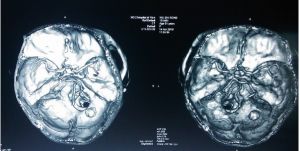

中風,腦損傷或腦腫瘤等多種健康問題會導致腦鈣化。甲狀旁腺功能減退是一種體內甲狀旁腺水平異常低的疾病,也與腦鈣化存在一定聯繫。

腦鈣化的症狀因人而異,並取決於大腦中沉積的鈣數量。法爾綜合徵這種遺傳性疾病是鈣沉積在大腦皮層和基底神經節的腦鈣化常見表現之一。大腦皮層在意識,記憶和知覺,以及其它功能方面扮演一個重要角色;而基底神經節在行動控制和眼睛運動等功能方面很重要。

因此,腦鈣化的症狀往往包括這些功能的問題。精神病學症狀涉及輕微的記憶錯誤或注意力集中能量降低,以及更嚴重的老年痴呆或精神病等。這些症狀往往在診斷前就會被發覺。此外,頭痛,眩暈,癲癇發作,以及運動和協調性問題也很常見。